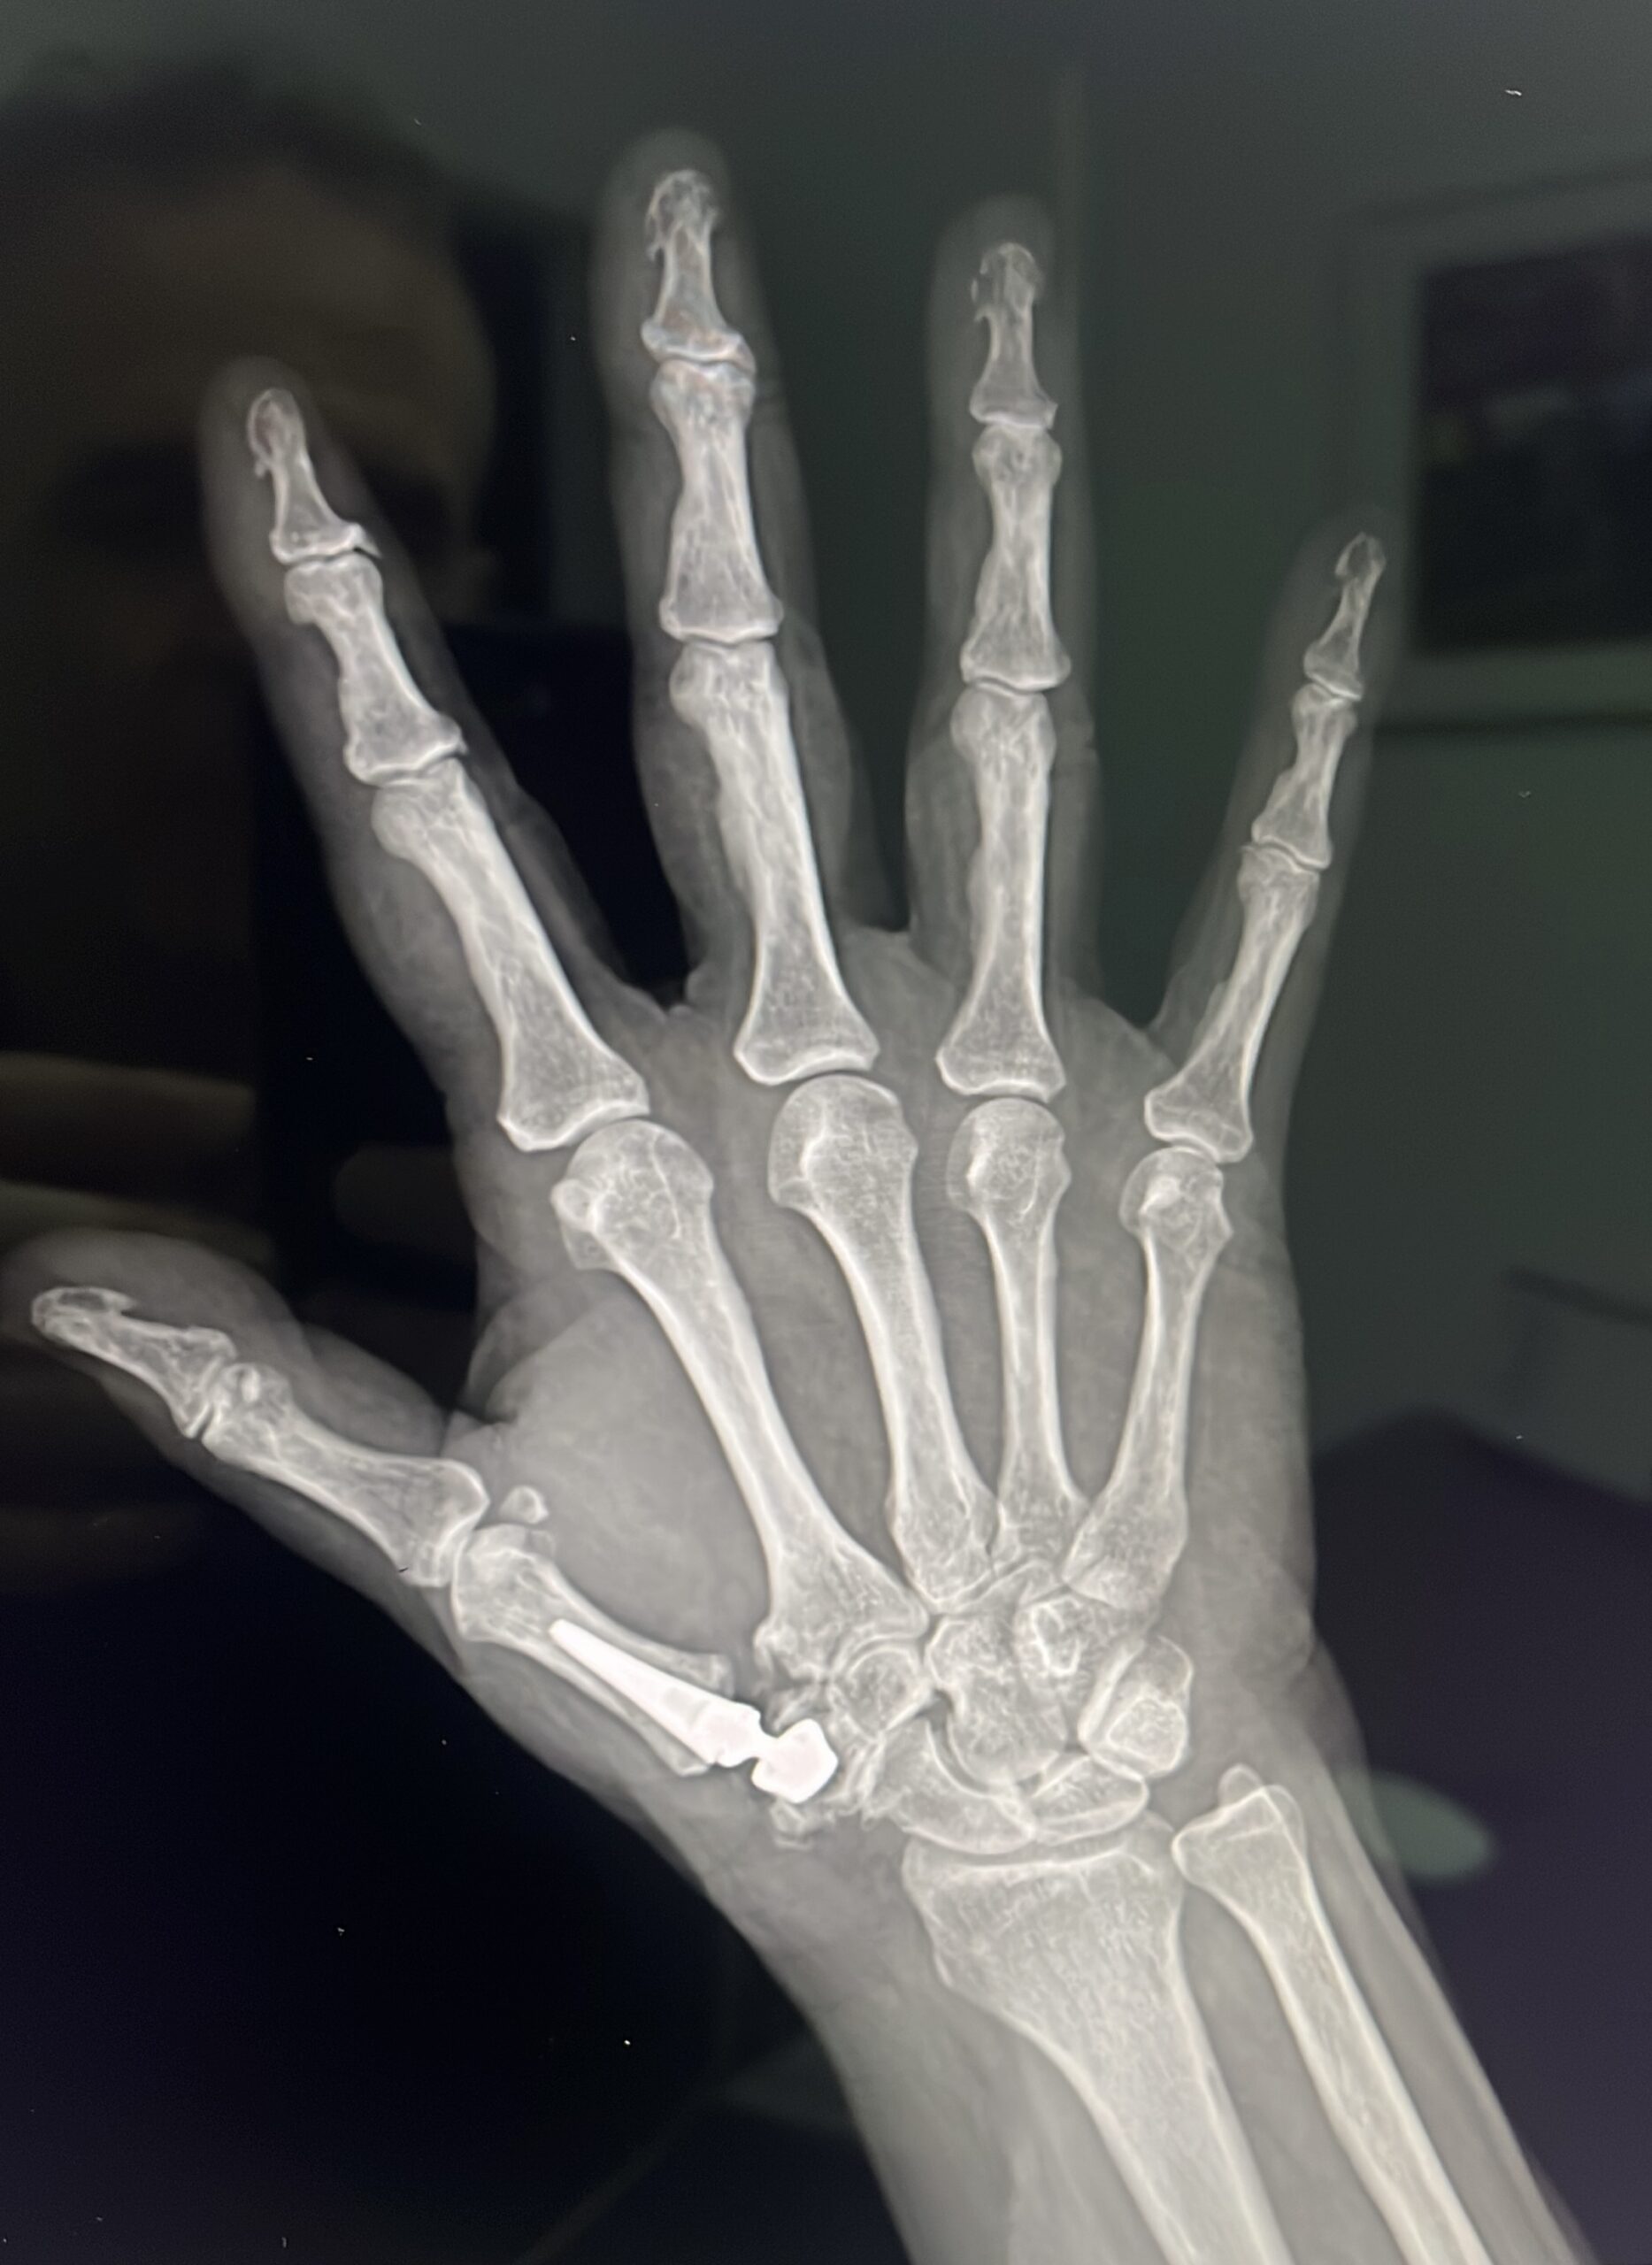

–Artroplastia total: Consiste en colocar una prótesis trapeciometacarpiana. El aspecto es similar a las que tienen las de cadera: hay un vástago que se coloca dentro del primer dedo, una cabeza esférica que articula sobre una cúpula llamada acetábulo que se coloca en el trapecio. La movilidad es completa y la fuerza también. Es la intervención que se ha realizado Nadal. De esta forma, ni pierde movilidad ni prácticamente fuerza, sobre todo de agarre. Esa articulación se ha desgastado debido al agarre de la raqueta y los golpeos todos estos años.

–Artrodesis de la base del pulgar: se usa en personas cuyos trabajos son de mucha fuerza. Consiste en dejar “sin juego” la articulación que une la base del dedo gordo con la muñeca, mediante una placa con tornillos. Si la articulación no se mueve, no duele. El trabajo de esa articulación que no funciona lo realizan otras pequeñas articulaciones de la muñeca, que deben estar sanas para poder realizar esa técnica.

–Artroplastia de interposición: Si el trapecio es el hueso de la muñeca que se encuentra dañado, lo extirpamos, sin más. Pero claro, ese hueso deja un espacio que rellenaremos con un tendón de la muñeca, que usamos como donante. Por eso se llama de interposición porque el tendón que usamos como injerto queda interpuesto entre el pulgar y el hueso de la muñeca. No hay problema porque en la muñeca solemos tener tendones que llamamos accesorios. Son aquellos que no deberían estar pero que suelen hacerlo. En la muñeca debe haber un tendón aductor únicamente, pues bien, la mayoría de las personas tenemos más de uno, así que usamos el que sobra. Cuando solo hay uno, usamos la mitad. De esta manera no debilitamos la zona donante. Esta técnica permite que la movilidad siga intacta y además la fuerza de agarre no se afecte. El posoperatorio consiste en estar inmovilizada la muñeca durante tres semanas y luego a realizar ejercicios de movilidad y agarre para poder hacer vida normal a las tres semanas.